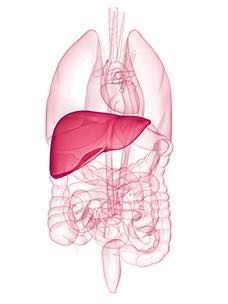

El hígado es un órgano vital, uno de los más importantes del organismo.

Desde el punto de vista anatómico, el hígado está situado bajo el diafragma y atraviesa la cavidad abdominal en toda su amplitud. El hígado es el órgano más voluminoso del organismo: pesa entre 1400 y 1600 g y mide unos diez centímetros en su punto más alto.

Está dividido en dos partes por el ligamento falciforme: el lóbulo derecho y el lóbulo izquierdo. La vesícula biliar está situada a nivel del lóbulo derecho y sirve como depósito de la bilis. El hígado y la vesícula biliar están unidos al intestino por el canal colédoco formado por la fusión de las vías biliares intrahepáticas.

El hígado es el único órgano que recibe sangre de dos fuentes: la arteria hepática, que aporta la sangre procedente del corazón, y la vena porta, que aporta la sangre procedente de los intestinos. La sangre sale del hígado por las venas hepáticas.